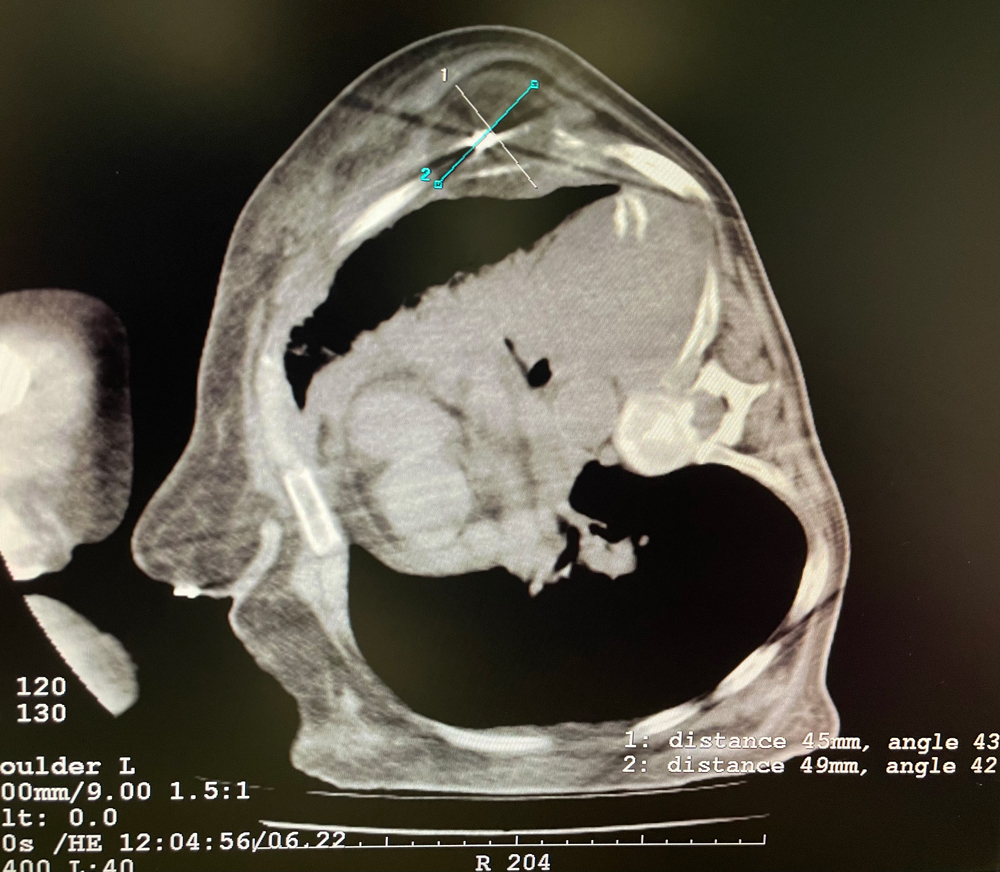

患者二

女,42岁,复发性脂肪瘤,病灶位于右侧膝关节,直径大小13cm。采用双针方案,共进行6个冻融循环,最大冰球直径达8.2cm,术中多方位治疗全面覆盖病灶范围。患者术后状况良好。